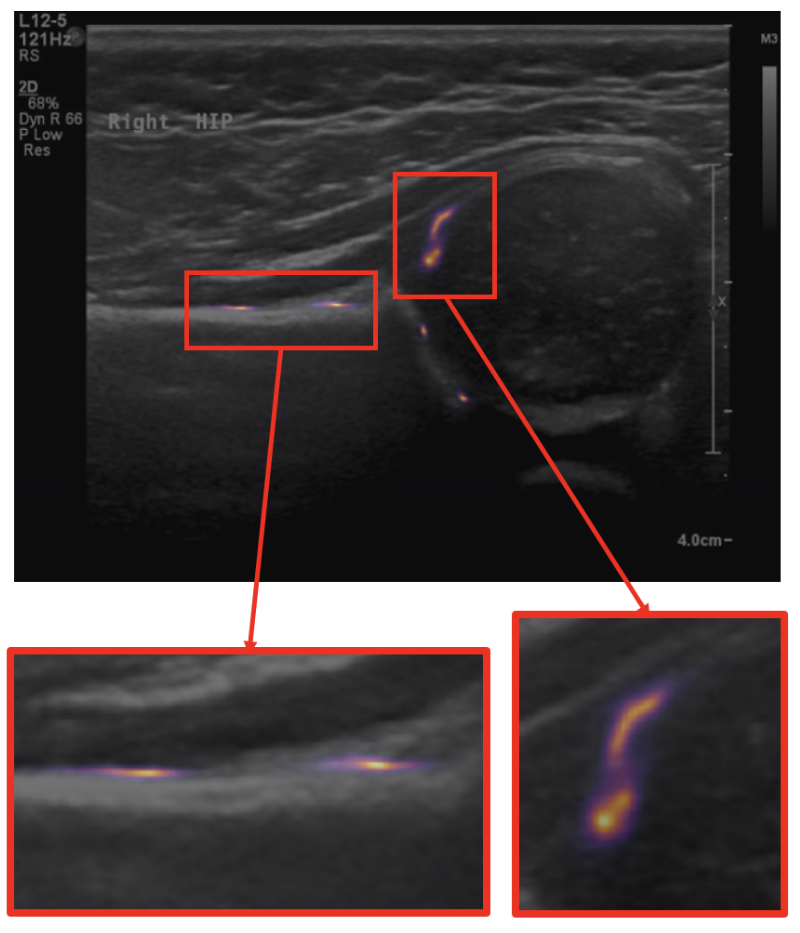

Ultrasound

Recent work has involved the study of ultrasound scans of infant hips, with a view to screening for developmental dysplasia of the hip (DDH). This work has scope for being translated into clinics.